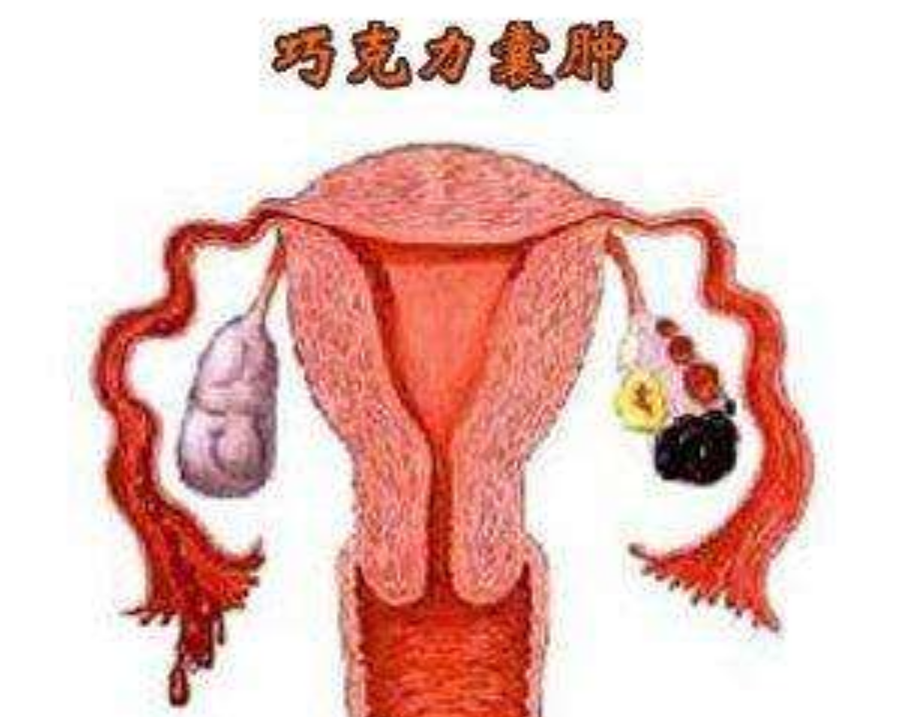

巧克力囊腫圖片

巧克力囊腫

子宮巧克力囊腫

子宮肌瘤巧克力囊

雙側巧克力囊腫

輸卵管巧克力囊腫